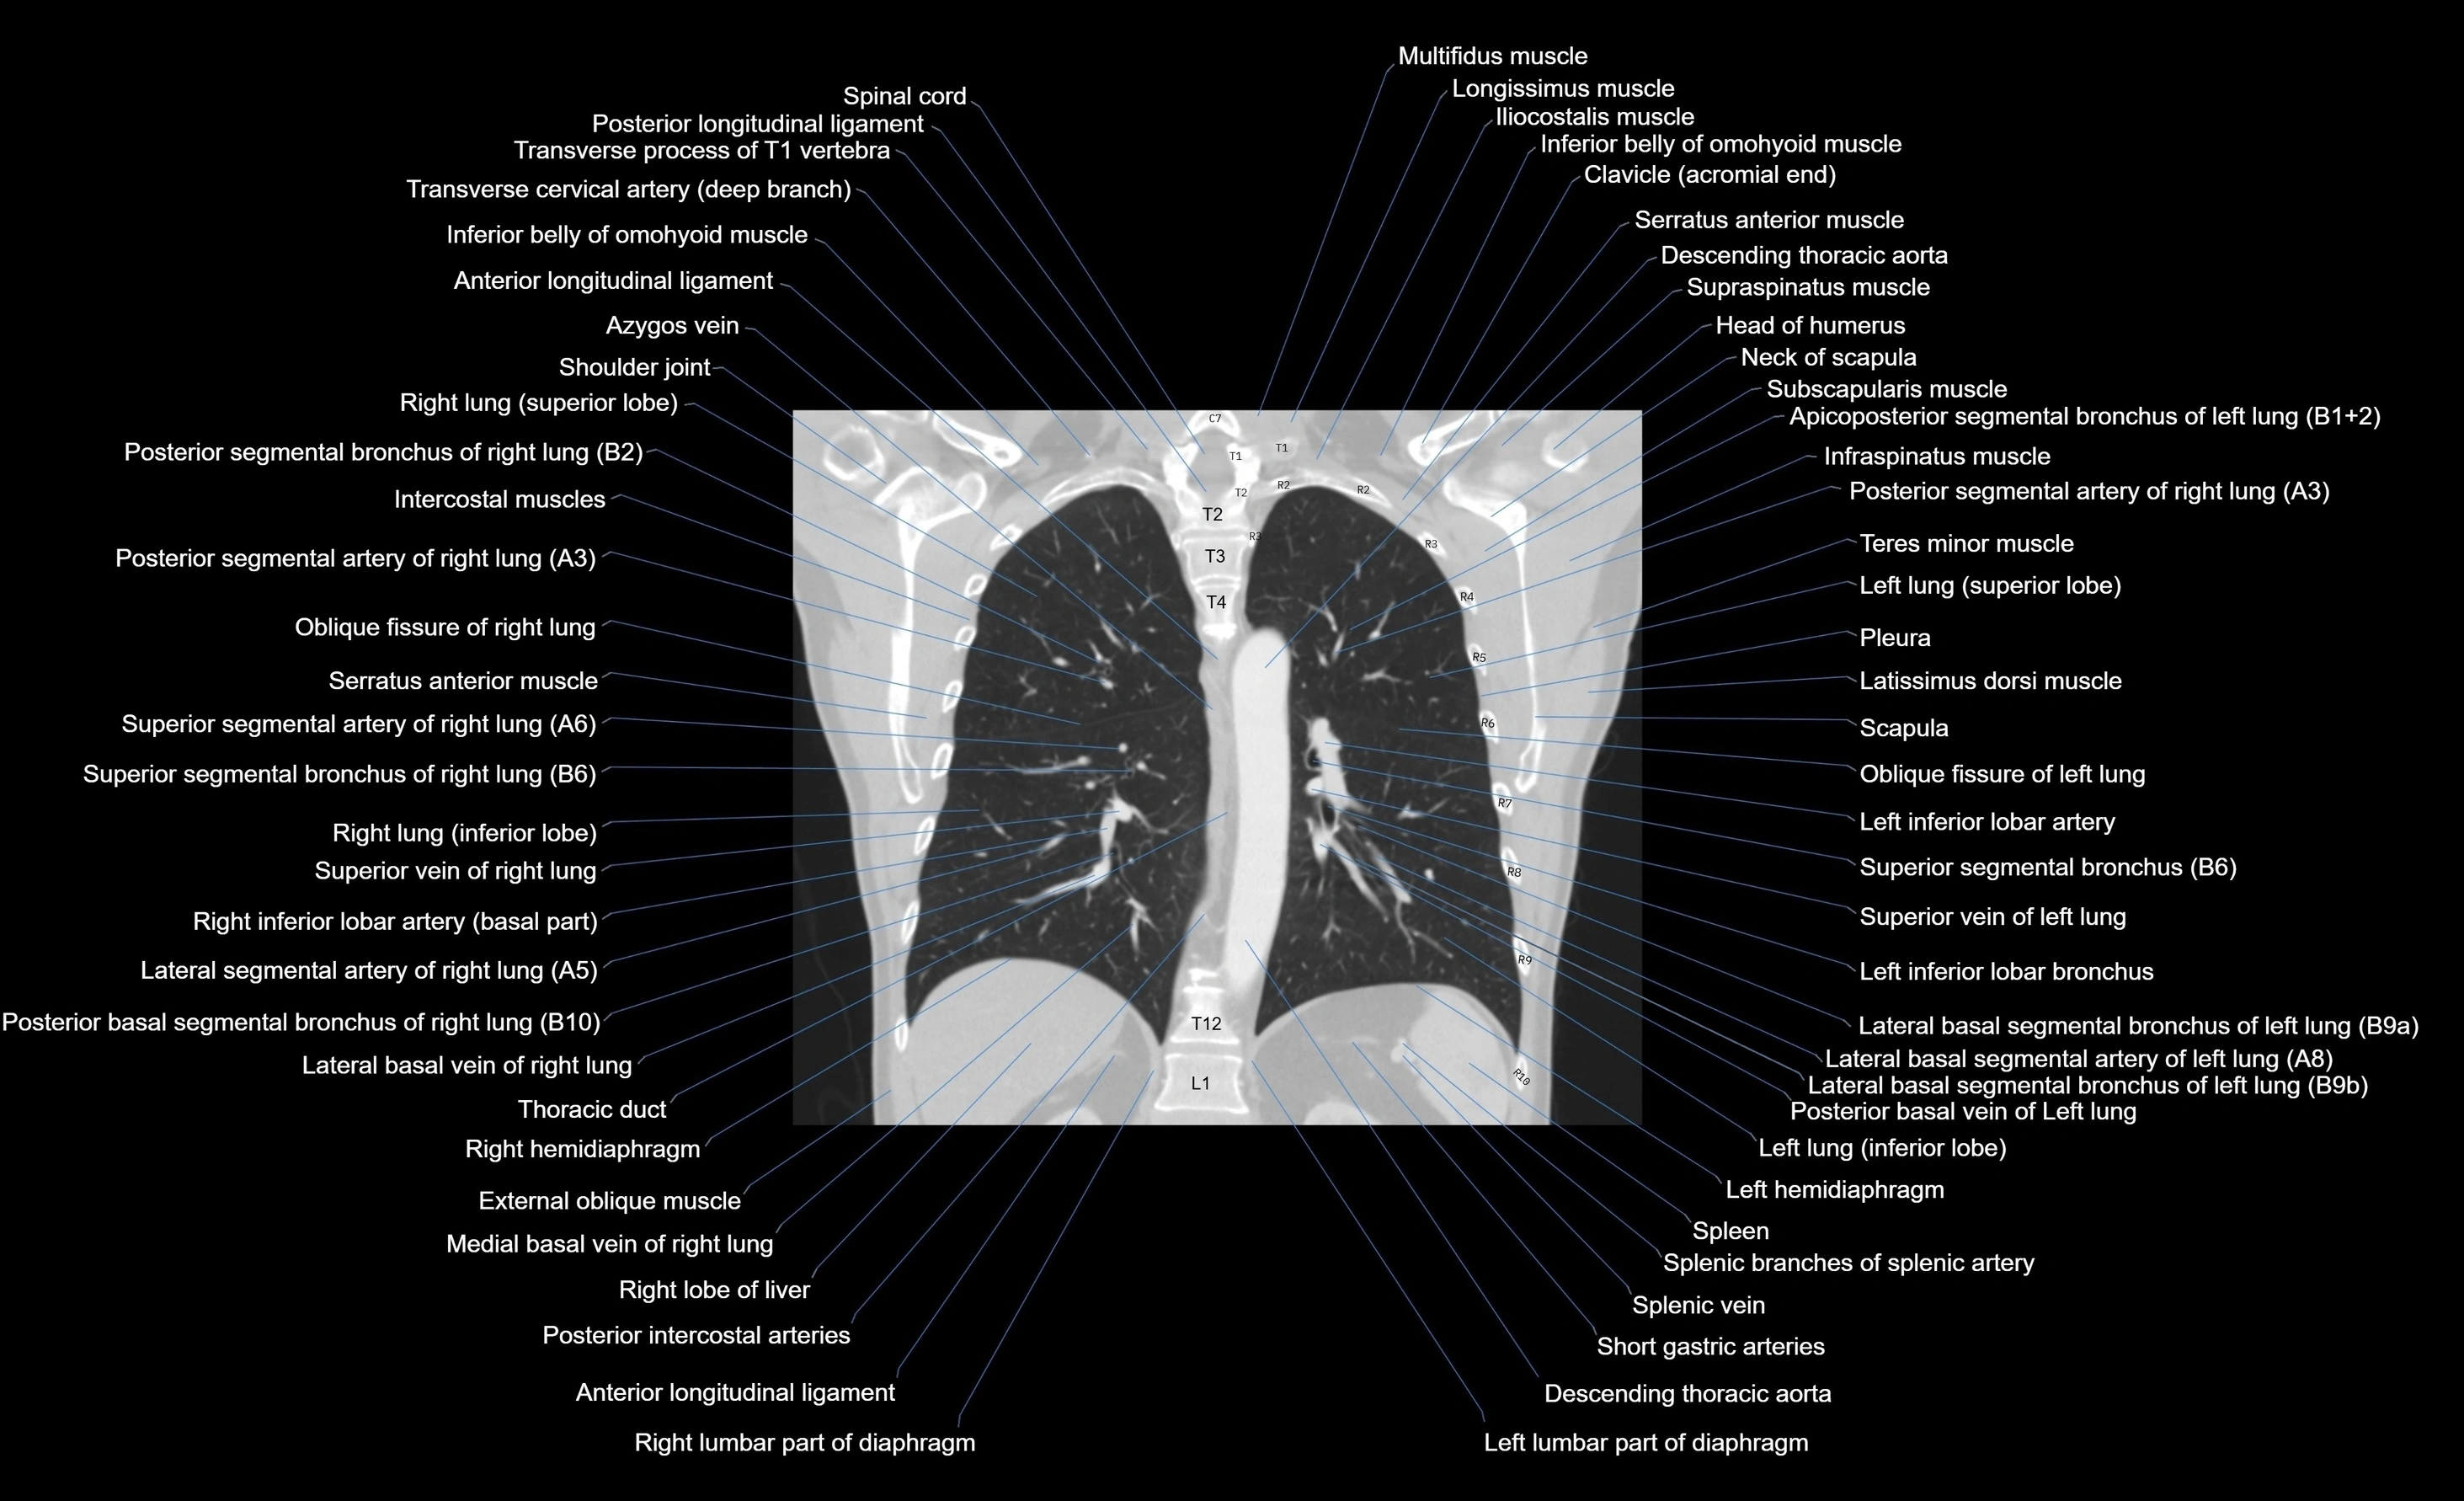

- Descending thoracic aorta

- Inferior lobe of left lung

- Inferior lobe of right lung

- Left hemidiaphragm

- Oblique fissure of left lung

- Oblique fissure of right lung

- Right lobe of liver

- Spleen

- Splenic artery

- Splenic branches of splenic artery

- Splenic vein

- Thoracic duct